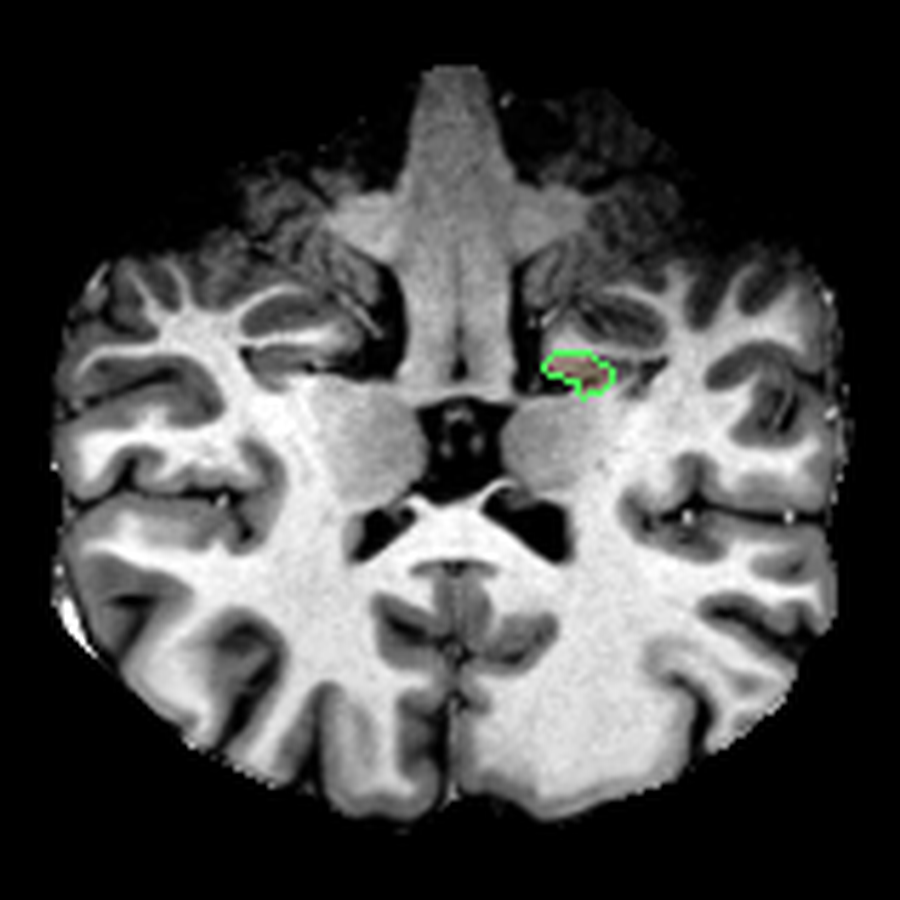

What I liked about having this data was that it changed how I interacted with the scan. Instead of staring at individual slices and guessing at the composition, I could start isolating specific parts of the brain.

The visualisations above show how little differentiation some brain regions have from their surroundings - I knew roughly where the thalamus was in the brain, but would never have been able to point it out on the MRI. At this stage, FreeSurfer plus some code had given me a perspective that would have been impossible for me to achieve myself.